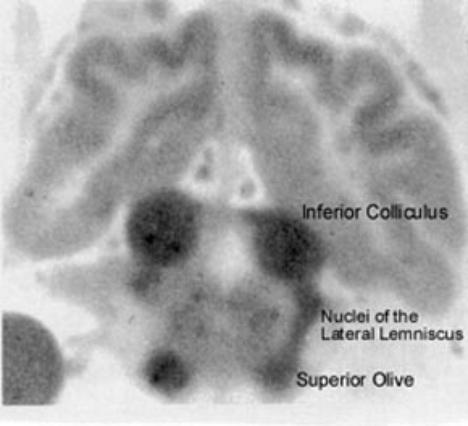

Figure 1:  Blood Flow in the Brain.  Autoradiogram of the brain of a cat 60

seconds after injection of a radioactive tracer shows the greatest perfusion

(thus greatest blood flow) in nuclei of the brainstem auditory pathway.

From Kety SS. Regional neurochemistry and its application to brain function. In French, JD,

ed, Frontiers in Brain Research. New York: Columbia University Press, 1962. pp 97-120.